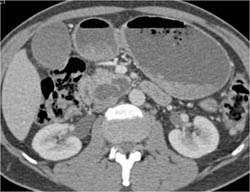

Intraductal Papillary Mucinous Neoplasm (IPMN)